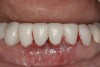

Two years later, however, the patient returned to her restorative dentist’s office complaining that “something felt different” on tooth No. 9. Localized moderate gingival inflammation was present on the facial aspect of No. 9 (Figure 12). A straight facial probing depth of 6 mm and severe bleeding on probing were also evident facially, suggesting a vertical root fracture.

Figure 12  Localized moderate gingival inflammation on facial aspect of No. 9 (2 years post-cementation).

Figure 12